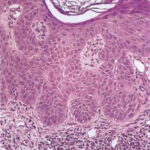

This variety of keratosis, sometimes referred to as florid keratosis, may easily be overdiagnosed as invasive squamous cell carcinoma by the unwary. Mild or moderate papillomatosis may be present. The epidermis is thickened in most areas and shows irregular downward proliferation that is limited to the uppermost dermis and does not represent frank invasion .A varying proportion of the keratinocytes in the stratum malpighii show a loss of polarity and thus a disorderly arrangement. Some of these cells show pleomorphism and atypicality (“anaplasia”) of their nuclei, which appear large, irregular, and hyperchromatic. Often the nuclei in the basal layer are closely crowded together. Some of the cells in the midportion of the epidermis show premature keratinization, resulting in dyskeratotic cells or apoptotic bodies characterized by homogeneous, eosinophilic cytoplasm with or without a nucleus. In contrast to the epidermal keratinocytes, the cells of the hair follicles and eccrine ducts that penetrate the epidermis within actinic keratoses retain their normal appearance and keratinize normally. Occasionally, cells of the normal adnexal epithelium extend over the atypical cells of the epidermis in an umbrella-like fashion. In some cases, abnormal keratinocytes extend downward on the outside of the follicular infundibulum to the level of the sebaceous duct and, less commonly, along the eccrine duct . |

A variant of the hypertrophic type of actinic keratosis is the lichenoid actinic keratosis, which demonstrates nuclear atypia, irregular acanthosis and hyperkeratosis, the presence of basal cell liquefaction, degeneration of the basal cell layer, and a bandlike “lichenoid” infiltrate in close apposition to the epidermis . Fairly numerous eosinophilic, homogeneous apoptotic bodies are seen in the upper dermis as so-called Civatte bodies. Aside from the presence of nuclear atypicality, |

there is considerable resemblance to lichen planus and benign lichenoid keratosis. An additional distinguishing feature may be the presence of plasma cells in the lichenoid infiltrate. |

The bowenoid type of actinic keratosis is histologically indistinguishable from Bowen’s disease and may also be referred to as squamous cell carcinoma in situ. As in Bowen’s disease, within the epidermis there is considerable disorder in the arrangement of the nuclei, as well as clumping of nuclei and dyskeratosis